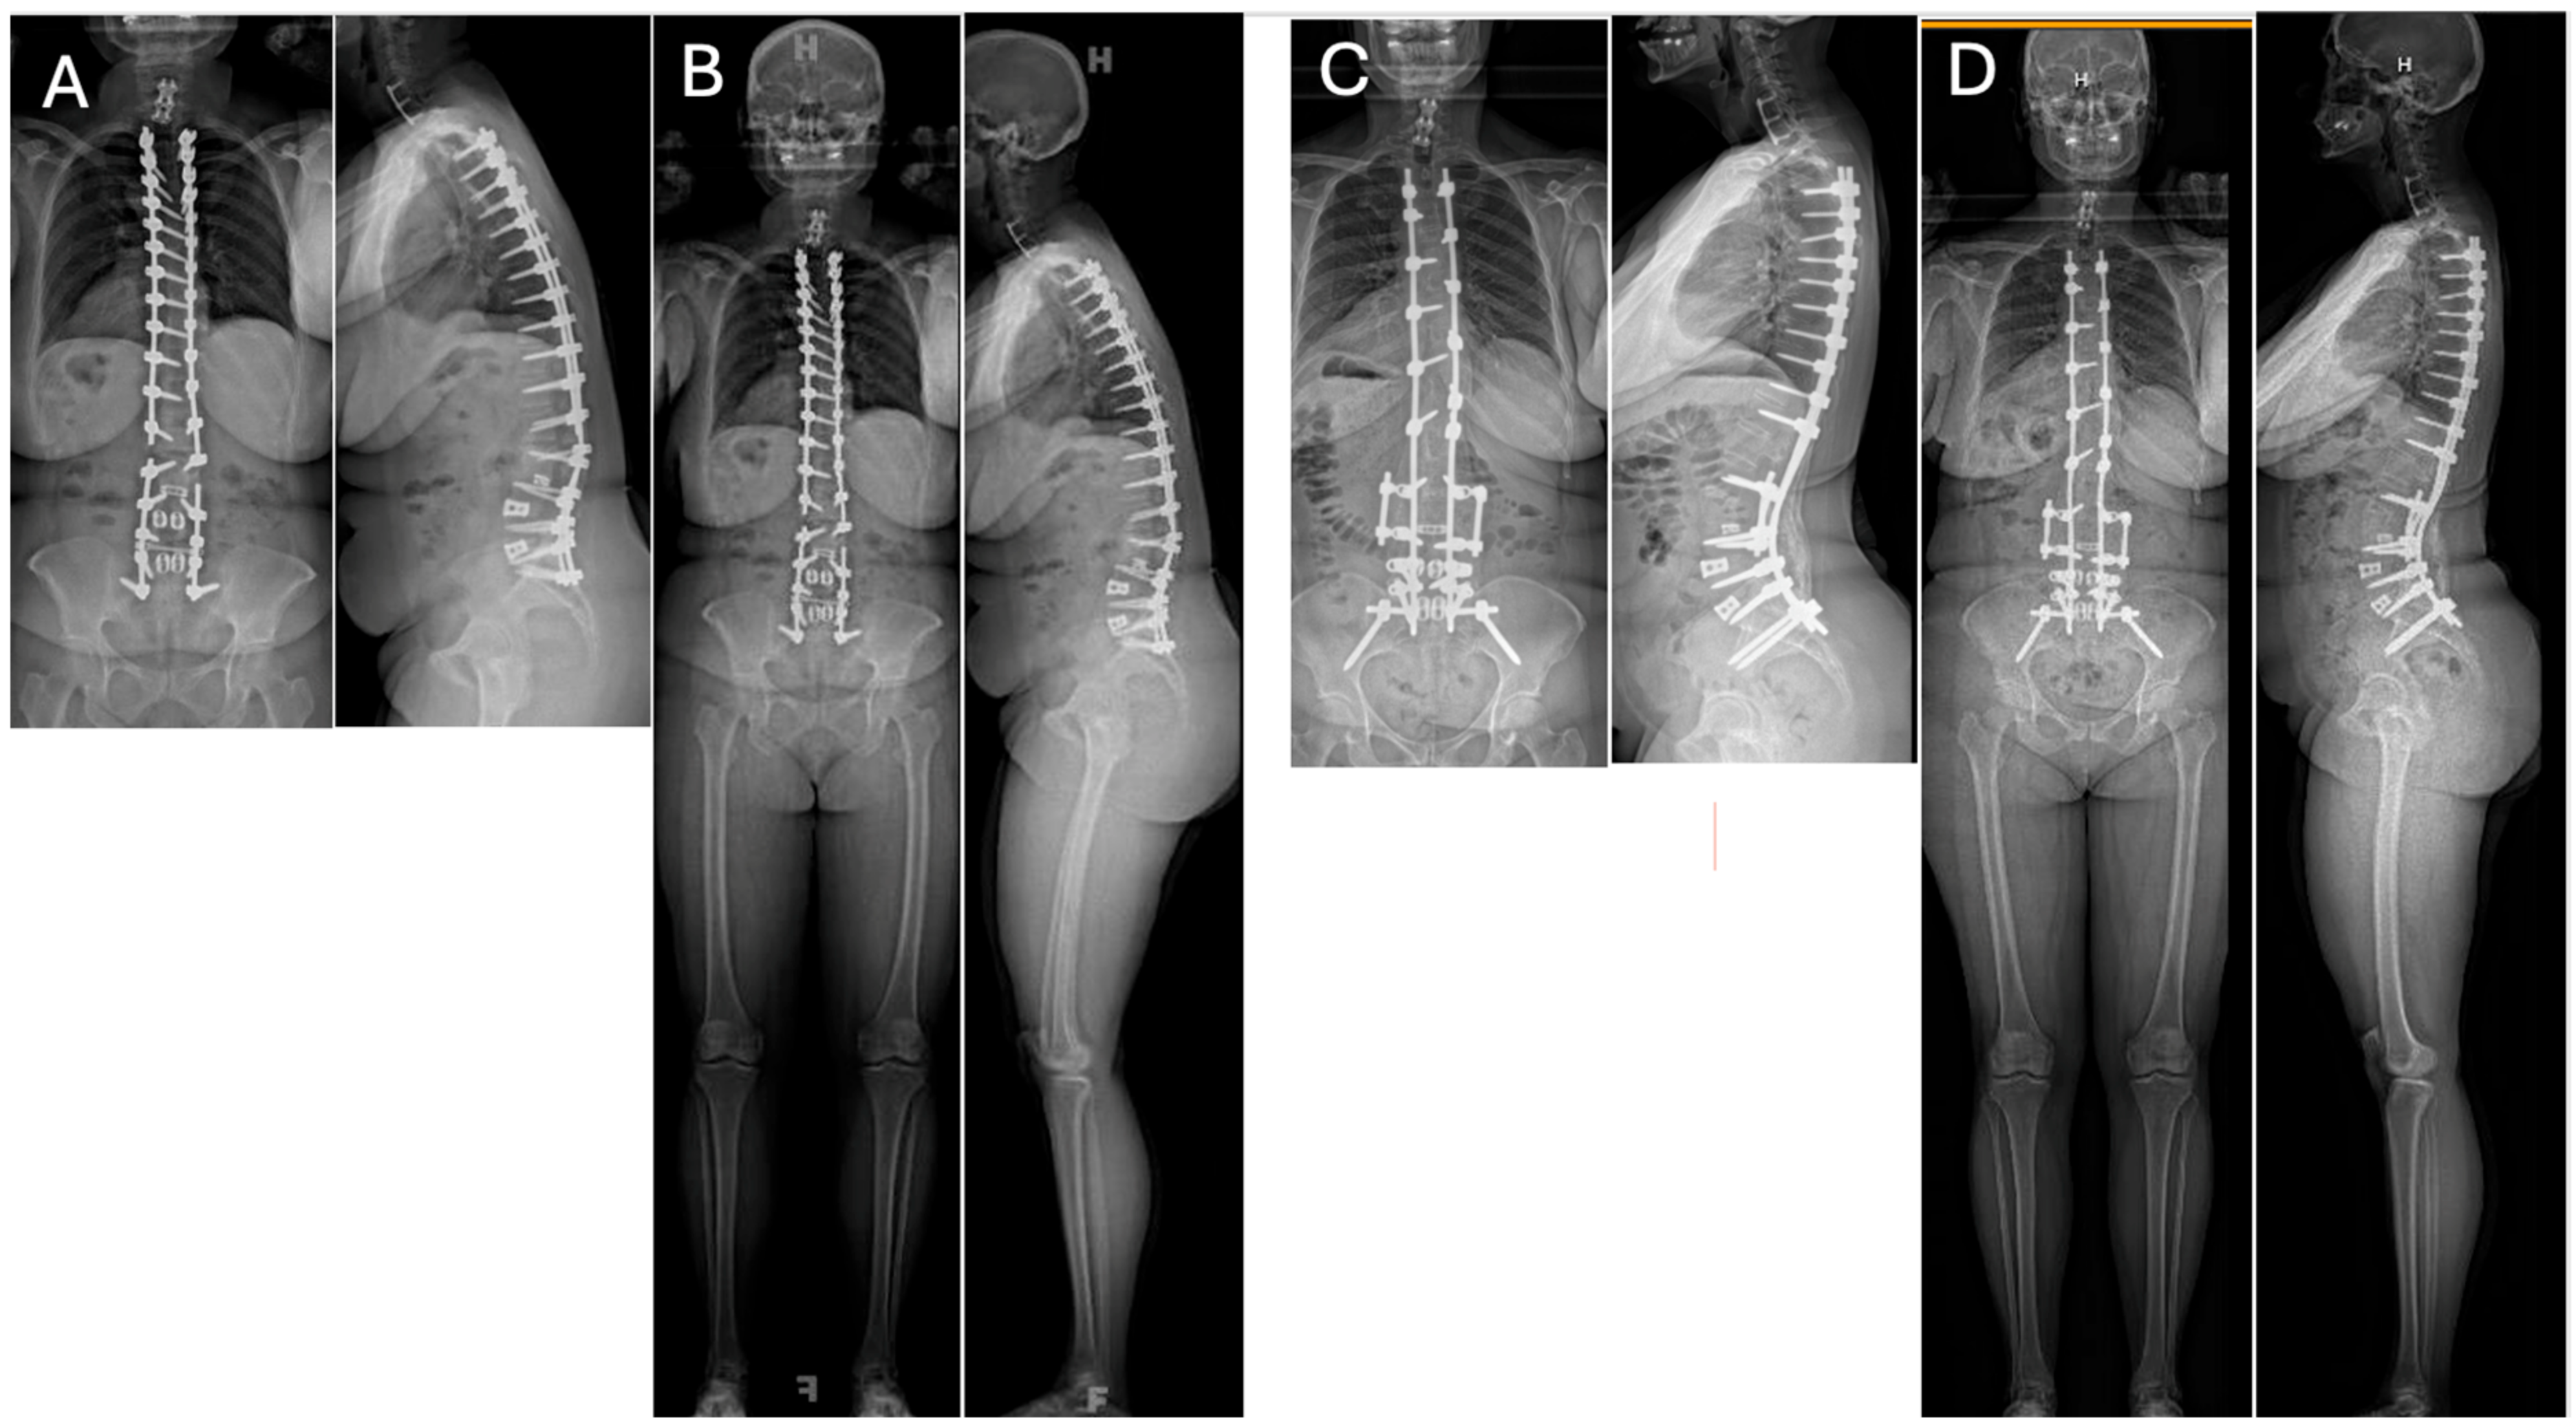

2. Part I: Rod Fracture

2.5. Treatment Strategies

2.6. Prevention Strategies